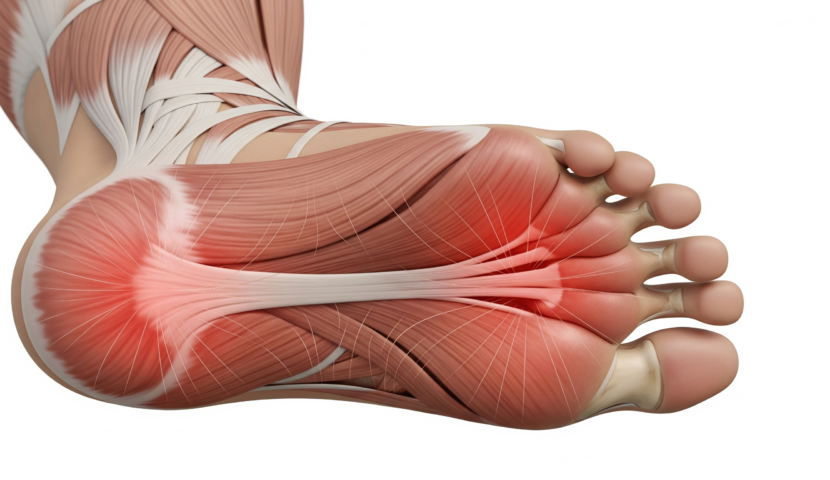

足底腱膜炎とは

足の裏にある腱膜という組織が炎症を起こすことで、かかとから土踏まずにかけて痛みを感じる疾患です。

足底腱膜炎の主な原因は、長時間の立ち仕事や歩行、硬い床の上での生活、靴のクッション性不足などです。